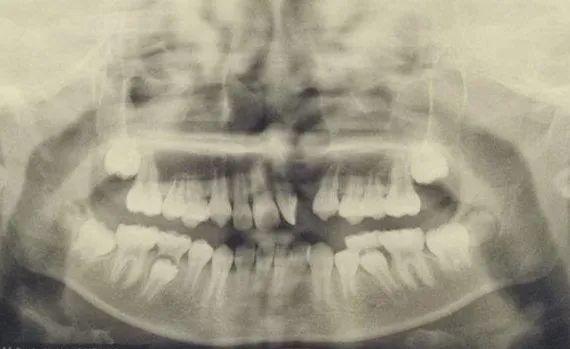

1、術(shù)前需要完善上頜骨全景片或上頜骨CT,了解上頜骨骨質(zhì)缺損情況,可提前預(yù)估手術(shù)難易及髂骨采取量。